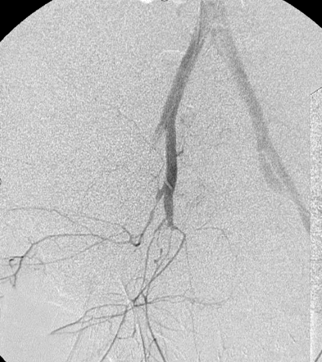

所有年龄超过 40 岁的患者, 卵巢受损 14%-43% 研究中闭经发生率(15%)与单纯UAE报告相似,可能与患者年龄(≥45岁)及卵巢储备自然下降有关。 ![]() 50岁,长期因子宫肌瘤导致月经出血过多,痛经和贫血。 子宫肌瘤栓塞术前,显示双侧子宫动脉发育不全,子宫肌瘤双侧卵巢动脉。 经皮股动脉穿刺双侧卵巢动脉栓塞,先500μm-700μm emboSphere 微球 术后4周,和6月的中短期随访,月经正常,子宫容积减少,贫血纠正,无卵巢功能衰竭。但看起来非灌注容积较少。 术后9月,由于子宫肌瘤持续存在,患者自己希望绝经,行全子宫和双侧卵巢切除术 术后病理,子宫内可见栓塞微粒伴有坏死,卵巢内也见栓塞微粒,但卵巢功能未受损。